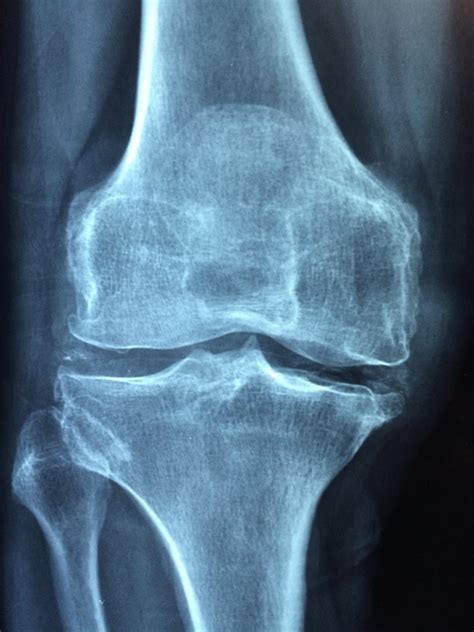

Wenn Sie eines oder mehrere dieser Symptome bei sich bemerken, ist es wichtig, einen Arzt aufzusuchen. Die Diagnose von Knochenkrebs erfolgt in der Regel durch eine Kombination von körperlichen Untersuchungen, Bildgebungstests wie Röntgenaufnahmen oder MRTs und Biopsieproben. Die Behandlung von Knochenkrebs kann je nach Stadium und Art des Tumors eine Kombination aus Operation, Strahlentherapie und Chemotherapie umfassen.